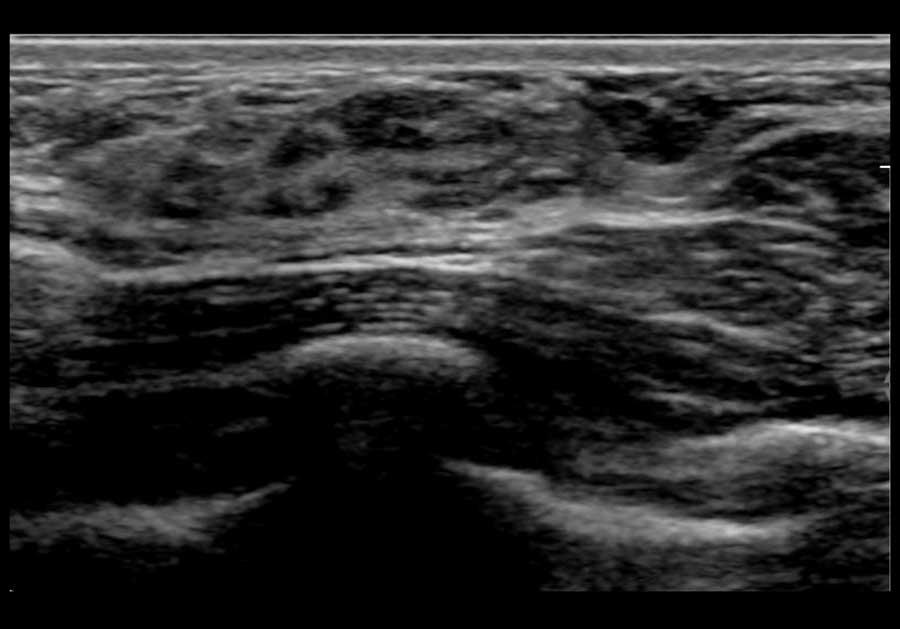

Đây là hình ảnh siêu âm bình thường của tuyến vú.

Lớp xám phía trên là da.

Tiếp theo là sự pha trộn giữa mô mỡ (tối hoặc giảm âm) và mô tuyến (xám sáng hoặc tăng âm).

Lớp có vân sọc phía sau mô vú là cơ ngực.

Phía sau hoặc sâu hơn so với xương sườn có một vùng đen hay bóng cản âm phía sau.

Phổi là lớp có thể quan sát sâu nhất.

Không khí trong phổi phản xạ hầu hết sóng âm, tạo ra một đường sáng hoặc tăng âm với bóng cản bẩn phía sau.